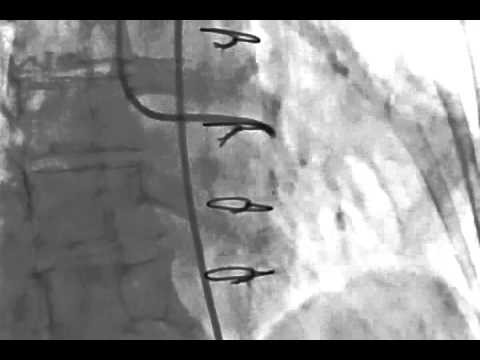

Video 7.1

Video 7.1: Left ventriculography with the MP catheter; RAO projection